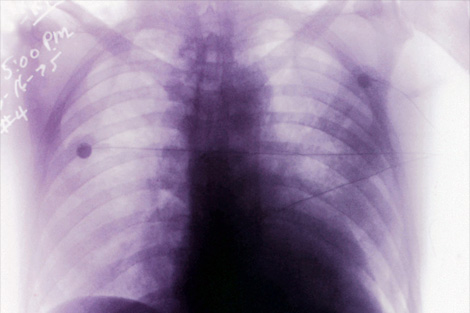

現在ウクライナでは謎のスーパーインフルエンザが大流行している。

死亡した患者の肺は炭のように黒く、内出血と肺水腫の症状があり、

第1次世界大戦後のスペイン風邪に状況がよく似ている。

ウクライナ政府の発表によると、

現地では16日の時点ですでに140万人が感染、315人が死亡しており、

近隣諸国のパニックを引き起こしている。

WHOの先週の論評では、現地のウィルスは突然変異していないとのことだが、

世界的流行病の第二波であると考えられているようだ。